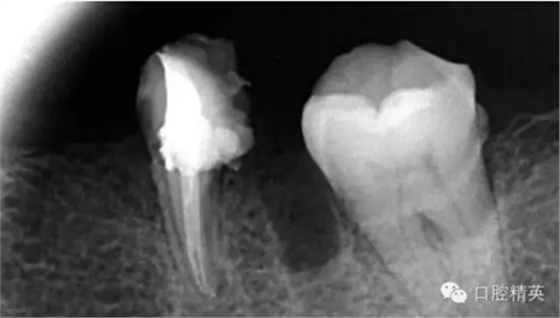

這個病例是我準備分根的病例,保留近中根,曾在外院做過干尸長達數(shù)十年。8號挫疏通時近舌根堵,近頰未找到。在這個病例中首先要知道是為什么根管難以疏通,首先是長時間的干尸,和患者年紀較大根管逐漸變窄,根管道路可能會出現(xiàn)堵塞,在這張病例中我能知道的是稍有不慎就會形成臺階,從而導致根管堵塞加重,更加難以疏通。

近舌8號k挫疏通,根尖部彎曲,我花費時間2小時疏通。我個人覺得根管能否被疏通,第一個重要因素是時間,因為作為牙體牙髓的醫(yī)生,首先就是需要的就是耐心。我個人覺得耐心是非常重要,因為很多根管被疏通時,都是我們快要放棄的時候。所以我每次都會安慰自己快好了,快好了,就差一點點,在堅持一會兒就好了。可以說沒有耐心,想做好牙體牙髓,我個人覺得很難很難。第二個就是手法,不知道大家啟用挫是什么挫,一般我個人認為,最好從8號開始疏通,這樣不容易在狹窄的根管內(nèi)形成臺階(如果有條件的可以從6號開始)。